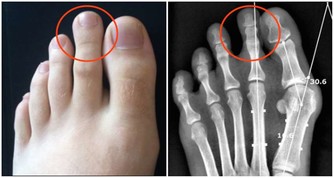

是由於變老的生理變化和病理變化,使患病的機率升高,衰老本身就是許多疾病的風險因素。

所以,變老不僅包括機體生理上的衰退,也包括在這個過程中發生的病理變化。